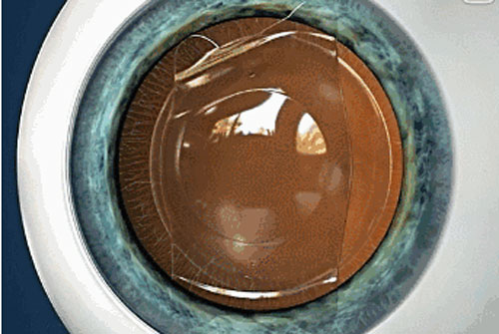

这是一种将特别定制的ICL晶体植入到眼内,来达到矫正近视、远视、散光等屈光不正问题的手术。不同于普通隐形眼镜,ICL晶体无需每天都摘下来,也没有每天佩戴不得超过8小时的要求,可以与人的眼睛和谐共处。

惠州希玛林顺潮眼科医院的ICL晶体采用的Collamer材料,Collamer为STAAR Surgical和EVO ICL产品所专有,是一种用来制作植入式晶体的生物相容性高的材料。

由于ICL的结构柔软且富有弹性,因此可轻松植入眼睛内,且能在眼中保持舒适自然。这种独特的 Collamer 材料会提供紫外线防护功能,同时不影响正常的视觉效果。